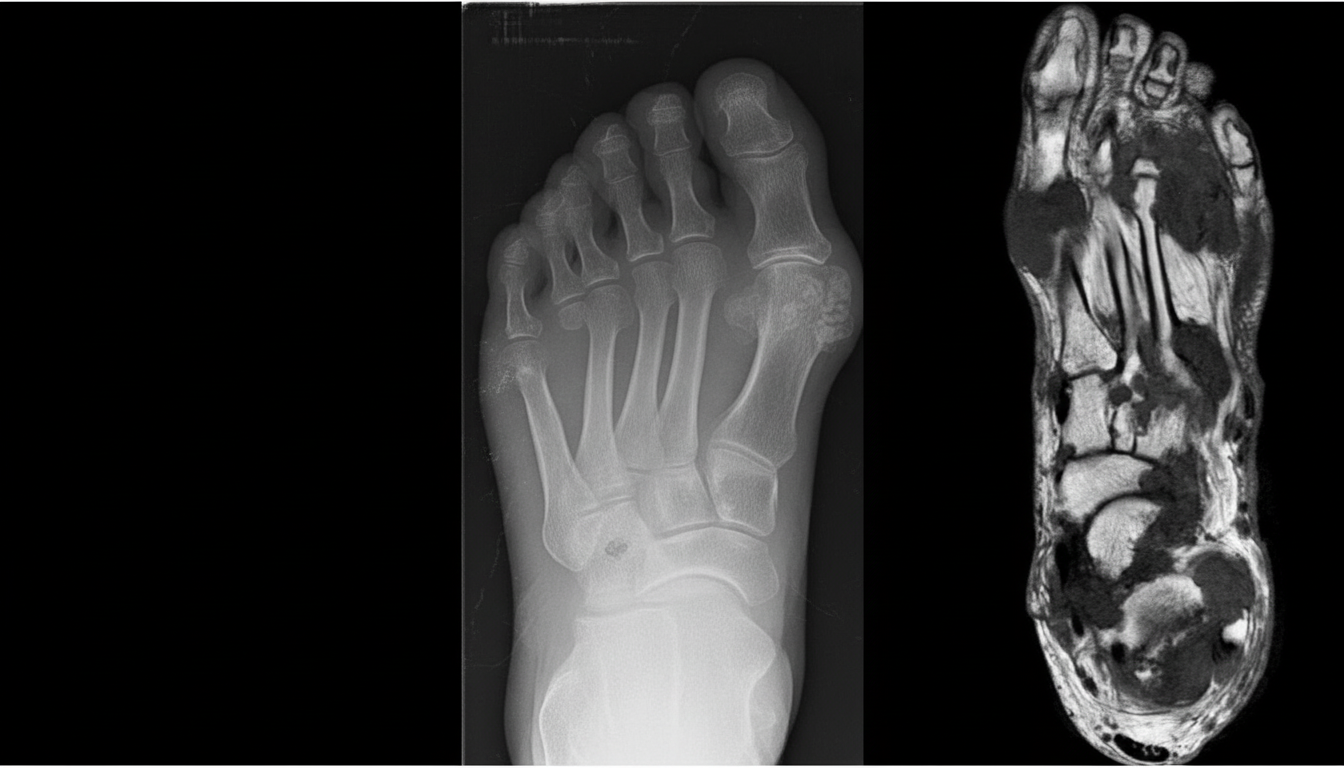

A person presented with swelling of the right 3rd toe. X-ray shows deposition of multiple crystals. A defect in which of the following pathways caused the problem?

Explanation: ***Uric acid pathway*** - Swelling of the toe with **crystal deposition** on X-ray is characteristic of **gout**, caused by **monosodium urate crystals** depositing in joints due to hyperuricemia. - Defects in **uric acid metabolism** lead to increased uric acid production or decreased excretion, resulting in crystal formation and joint inflammation. *Purine salvage pathway* - While **HGPRT deficiency** (Lesch-Nyhan syndrome) can cause hyperuricemia, it's a secondary effect rather than the primary pathway defect causing gout. - The purine salvage pathway defect would present with **neurological symptoms** and **self-mutilation** in severe cases, not isolated joint swelling. *Urea cycle* - The **urea cycle** is involved in **ammonia detoxification** and nitrogen disposal, not uric acid metabolism. - Defects cause **hyperammonemia** with neurological symptoms like confusion and coma, not crystal arthropathy. *CORI cycle* - The **CORI cycle** involves **lactate-glucose interconversion** between muscle and liver during exercise and fasting. - This metabolic pathway has no relation to **uric acid production** or crystal deposition in joints.